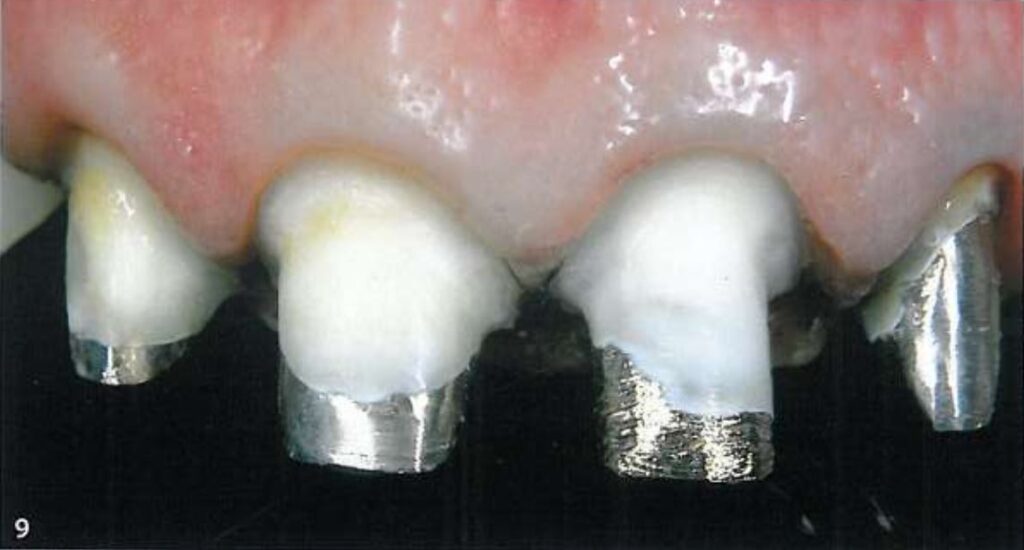

Hình 9 mô tả vị trí lí tưởng của 2 sợi chỉ trong khe nướu, khi đó khe nướu rộng sang bên > 0.5 mm và tách xuống dưới > 0.5 mm để cho phép ghi dấu 1 phần mô răng lành bên dưới đường hoàn tất.